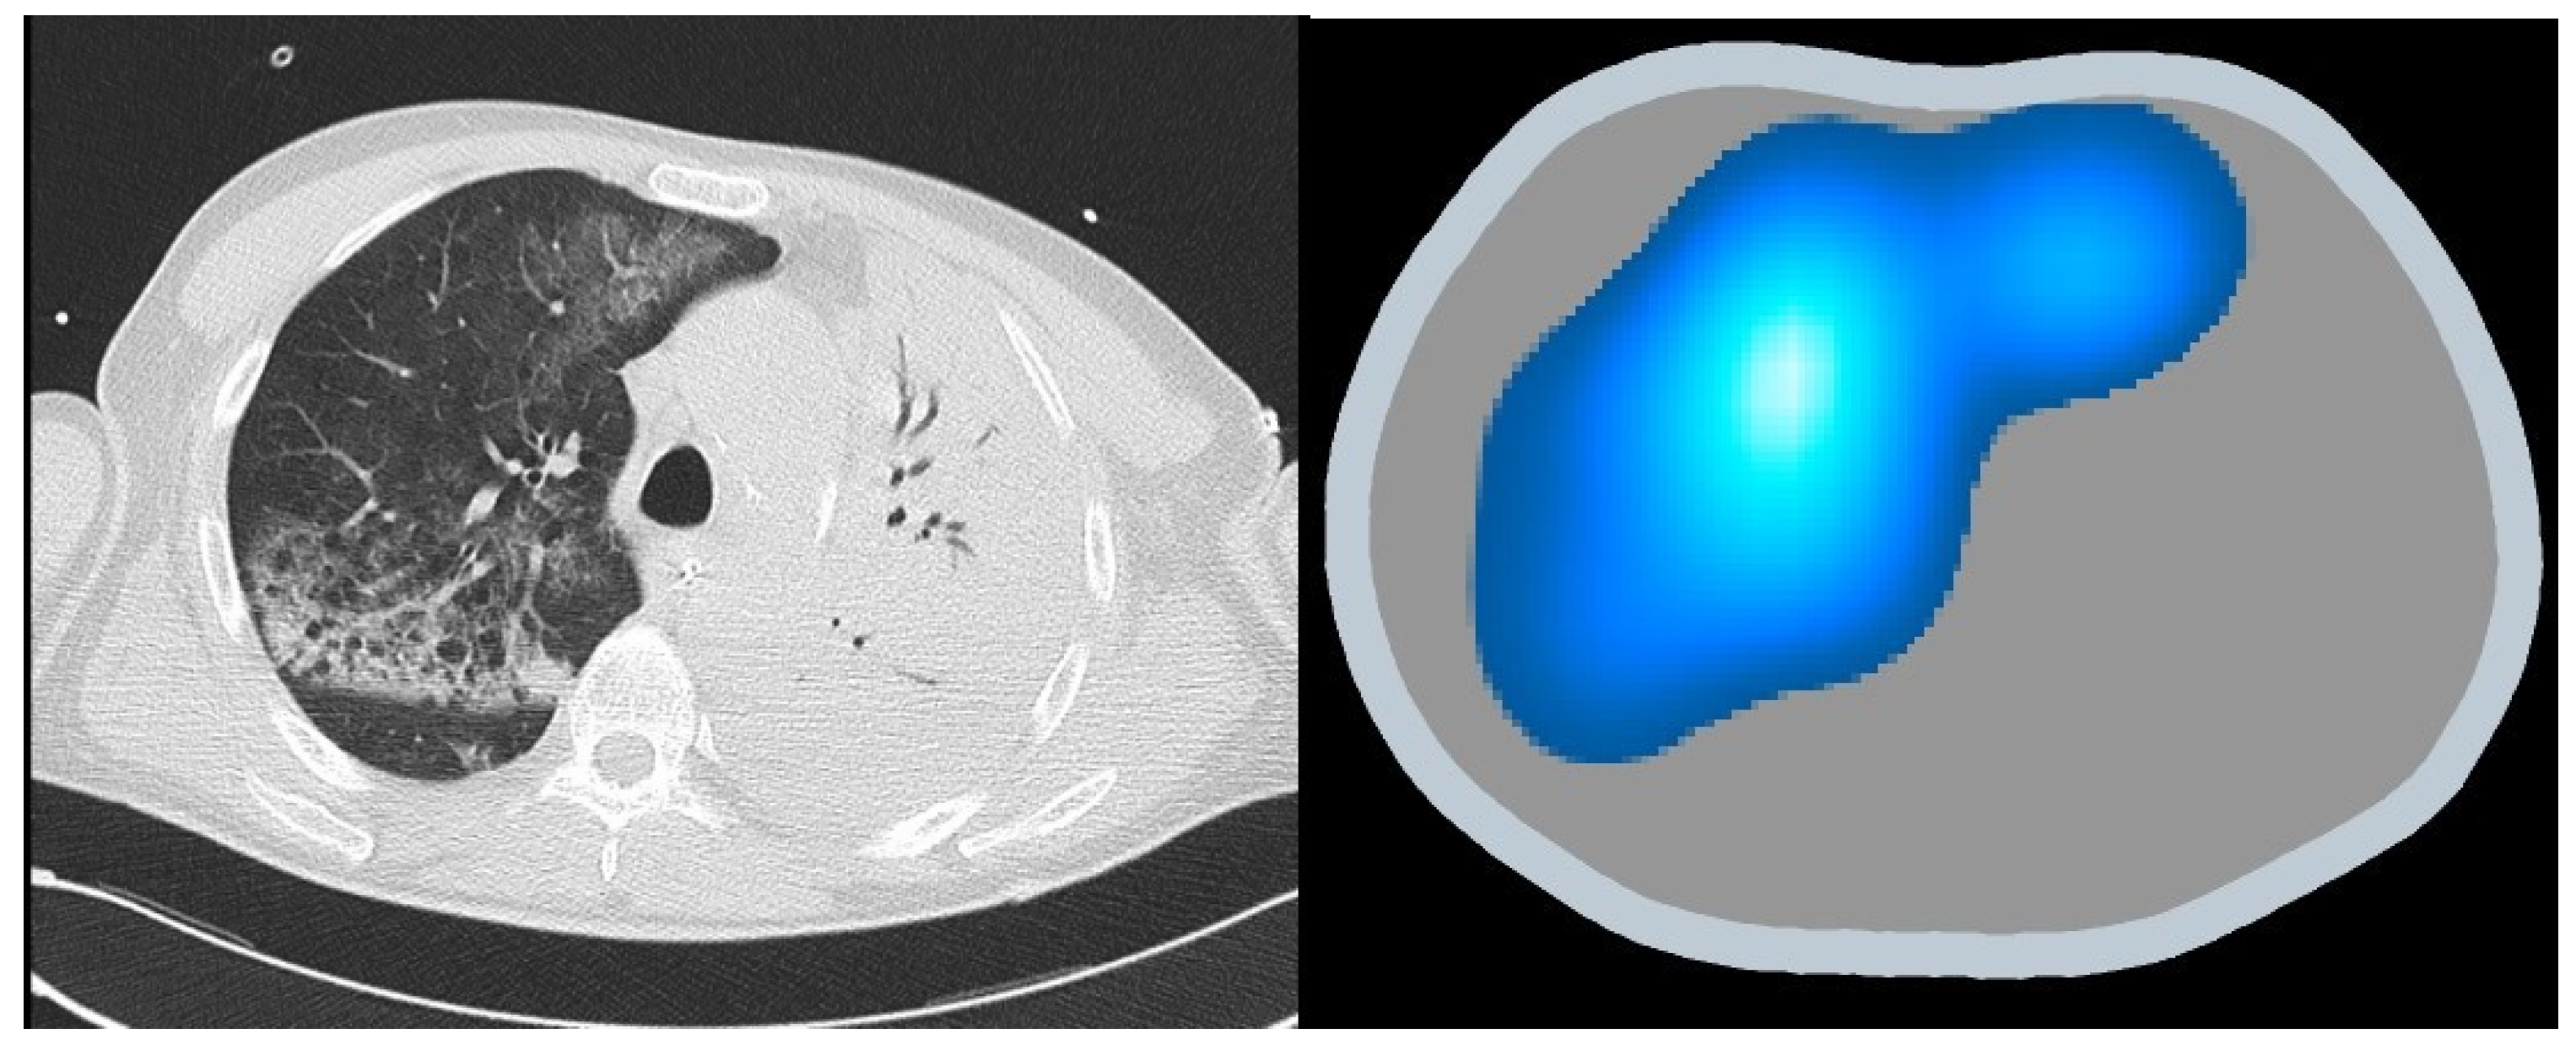

The incorporation of EIT within the schema of ARDS management heralds a paradigmatic shift towards a more individualized, data-driven ethos of care. This integration not only fosters a more profound comprehension of the pathophysiology underpinning ARDS but also augments the avenue for personalized therapeutic stratagems. The confluence of EIT’s real-time visualization and the data-driven insights it engenders marks a new era in the quest for a more refined and effective management of ARDS. Through the lens of EIT, the veil shrouding pulmonary inhomogeneities in ARDS is gradually lifted, thus offering a clearer sight for tailored therapeutic interventions (

Figure 6).

Figure 6.

Revealing lung inhomogeneities in ARDS: comparing CT scan with EIT.